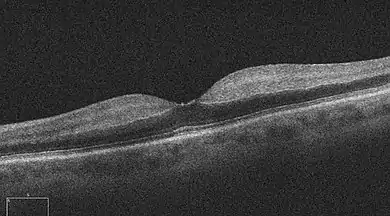

Ocular coherence tomogram (OCT) of a person with central retinal artery occlusion

One diagnostic method for the confirmation of CRAO is Fluorescein angiography, it is used to examine the retinal artery filling time after the fluorescein dye is injected into the peripheral venous system.[2] In an eye with CRAO some branches of the retinal artery may not fill or the time it takes for the branches of the retinal artery to fill will be increased, which is visualized by the leading edge of the fluorescein moving slower than normal through the retinal artery branches to the edges of the retina.[2] Fluorescein angiography can also be used to determine the extent of the occlusion as well as classify it into one of four types non-arteritic CRAO, non-arteritic CRAO with cilioretinal artery sparing, transient non-arteritic CRAO and arteritic CRAO.[3] Optical coherence tomography (OCT) may also be used to confirm the diagnosis of CRAO.[4]